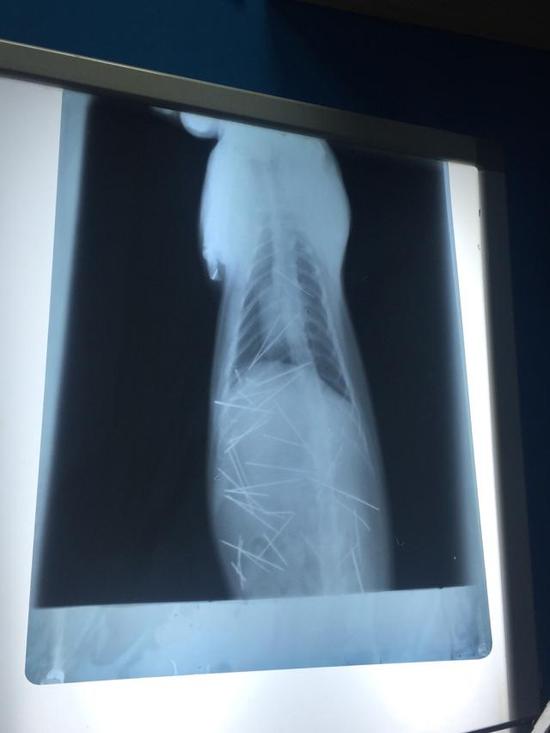

原标题:小猫体内插入40根针疑为气枪类工具打入 医生4小时取出

这是一个残忍而又暖心的故事。一位小姑娘发现她收养一年的小猫脖子后有凸起,到医院检查发现,小猫体内有多达30至40根针。广州某宠物医生判断,这些针不是手工插入,很有可能是用类似气枪的东西打入的。5月21日夜,手术完成,医生用了近4小时的时间,取出了43根针(包括断掉的针头)。主人表示,很多针都已经生锈。

这位生活在深圳的小姑娘是5月19日发现小猫异常的,她在当晚发出的微博有多张小猫的X光照片,其中密密麻麻的针看起来十分恐怖。观察者网注意到,她的这条微博已有3万余次转发。次日(20日),她带小猫来到深圳某宠物医院治疗,因为该院没有C型臂,所以又转至广州一家宠物医院。21日夜手术结束后,该宠物医院表示,7根针是在皮肤或肌肉,3根针和2个断端在胸腔心脏旁边。30根针在腹腔,其中有4根是插入到左侧肾脏。这是一个复杂的手术,为了这个可怜猫猫,X线连续曝光53次。